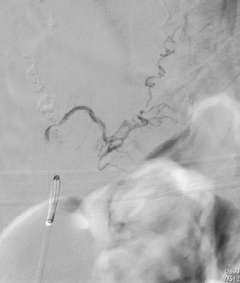

Figure 3: A palliative / partial Catheter Treatment for a Spinal AVM.

Figure 4: Catheter Embolization of a Spinal Dural AVF.